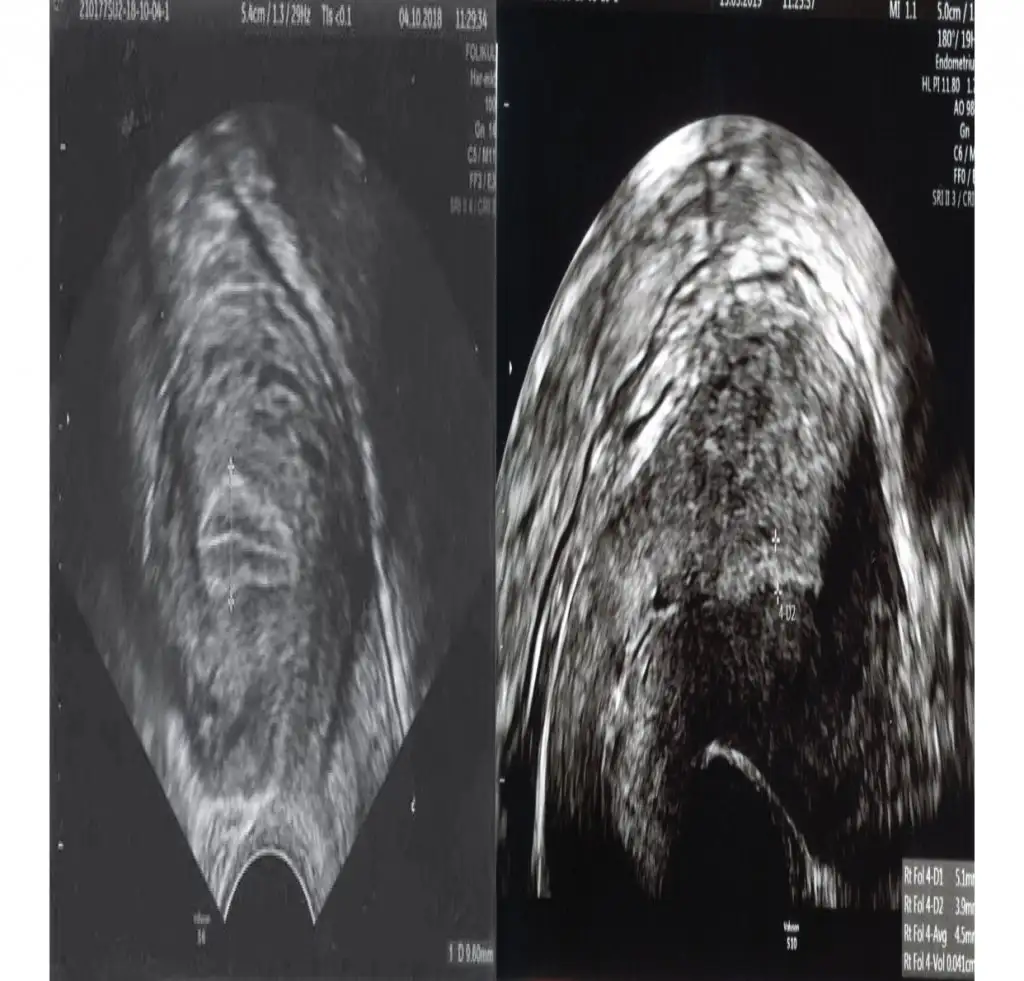

Soldaki 3 çizgi oluyor belirgin ve 2 tarafı eşit3 cızgı ne canım

Profum yetişti bilmediğin baska ne var seninSoldaki 3 çizgi oluyor belirgin ve 2 tarafı eşit

HmmmSoldaki 3 çizgi oluyor belirgin ve 2 tarafı eşit